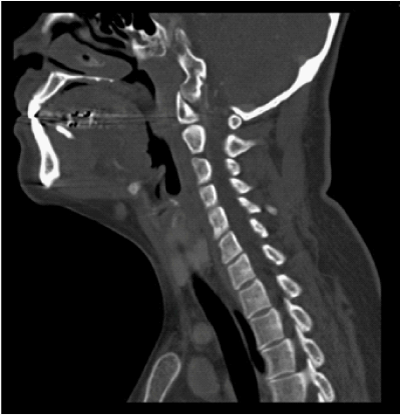

The CT showed a calculus in the region of distal submandibular duct measuring 5 X 3 X 13mm and evidence for acute inflammation (Figures 1&2). On further history taking, she has had no such similar episodes since the removal of her right submandibular gland and this was her first attack. She has also not noted any lump in her floor of mouth or neck in the past.

Figure 2 Computerised Tomography (CT) scan image of the patient showing the stone in the Wharton’s duct.